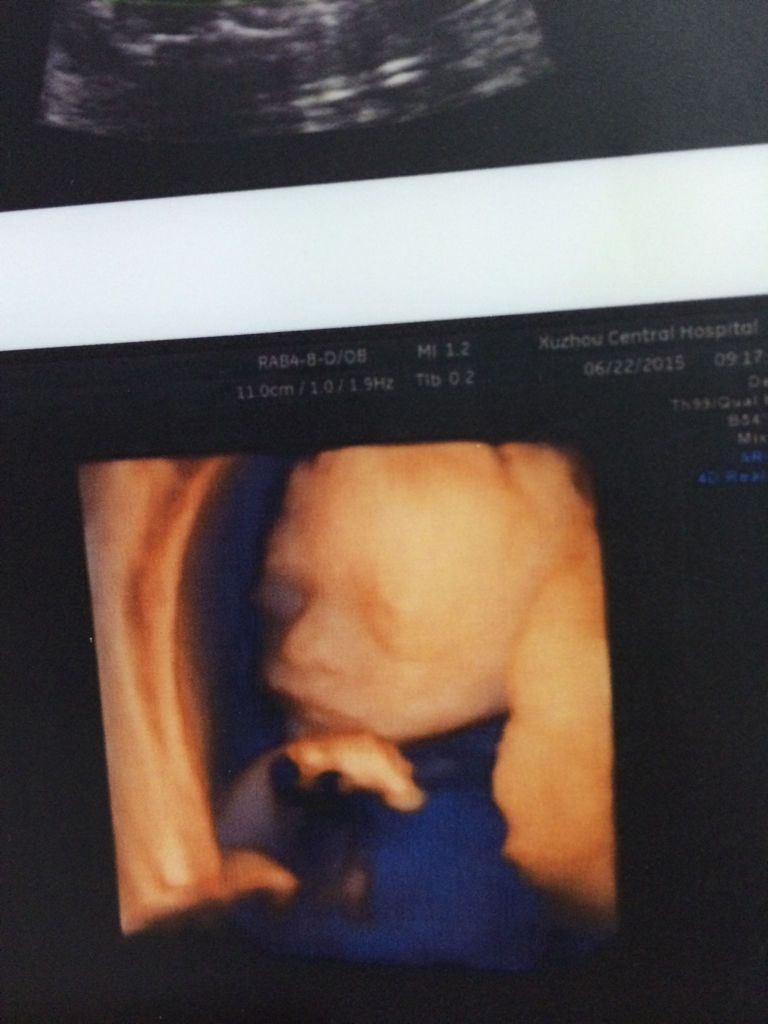

请问有懂彩超的朋友帮我看看这几张图是男宝还是女宝,真的很想知道,我不懂,我 真心的谢谢你们了,不多

请问有懂彩超的朋友帮我看看这几张图是男宝还是女宝,真的很想知道,我不懂,我 真心的谢谢你们了,不多说了,直接给分。

光贫这些看不出 男女要B超好久 翻动胎儿岩暖命姿势 全面看清胎儿 找锅眨到小鸡鸡才能确定 但不准确得 比较B超是机器 肉眼是看不清全部的 自己的总是好的 在乎男女查肿干什么